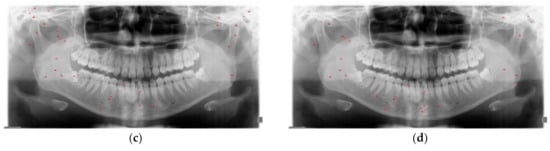

2.2.1. Data Augmentation